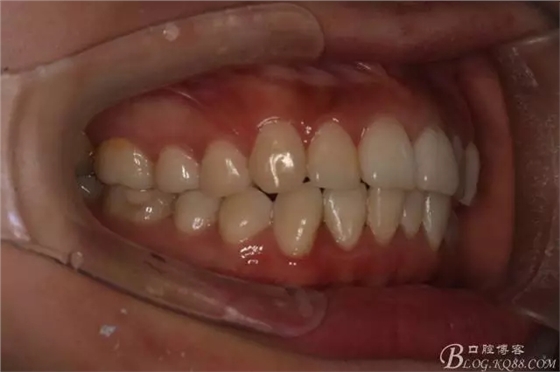

如圖,該病例為簡(jiǎn)單排齊病例,但77鎖合是矯治中的關(guān)鍵所在,你會(huì)怎么處理?

該病例主要為17、27頰側(cè)位同時(shí)伴有伸長(zhǎng),當(dāng)然種植支抗可以解決,但還有簡(jiǎn)單實(shí)用的辦法嗎?如圖,在橫腭桿遠(yuǎn)中延伸出牽引鉤,位置盡量遠(yuǎn)離合平面,7粘舌側(cè)扣,牽引力的方向?yàn)閴旱图吧嘞?,下圖為兩個(gè)月的效果,17已到位,27還未到位。